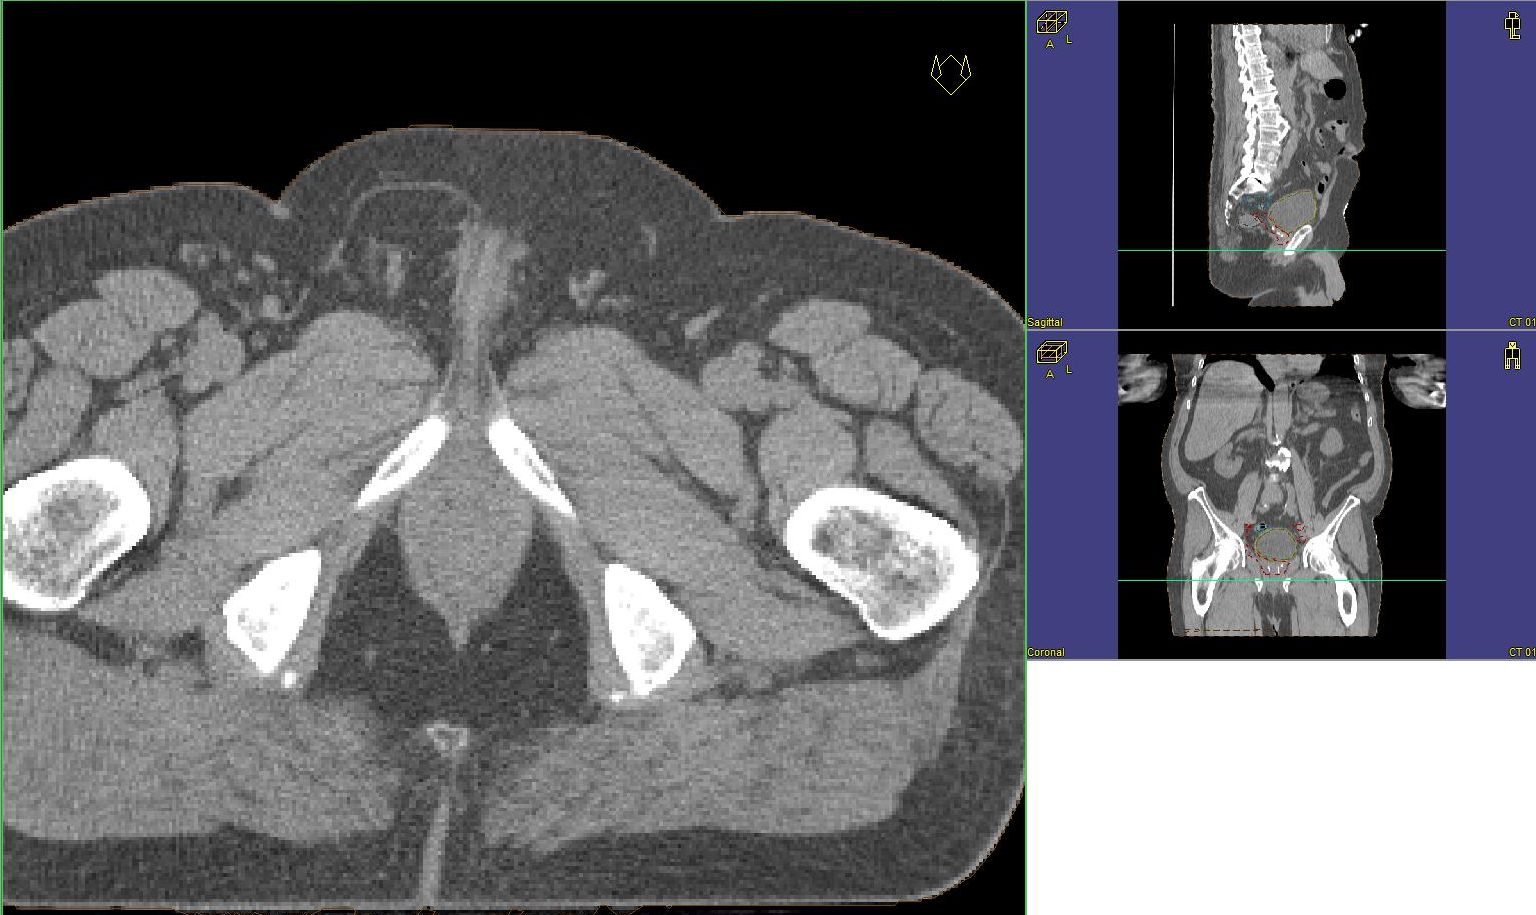

Prostata-Ca: Zielvolumen der postoperativen Radiotherapie

Beispiel: postoperative RT